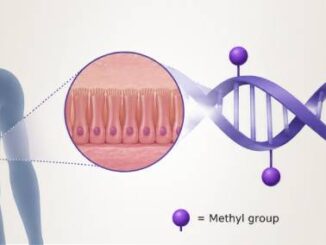

For years, scientists have studied why some organisms live longer than others. While genes play an important role in aging, research continues to show that lifespan is not determined by DNA sequence alone. The way genes are regulated, through epigenetic marks that [more...]

DNA Methylation Changes in the Aging Gut May Help Drive Cancer Risk

June 9, 2026The human gut is one of the body’s fastest-renewing tissues. Every few days, new cells are produced from intestinal stem cells to help maintain the lining of the gut. However, a study suggests that, with [more...]